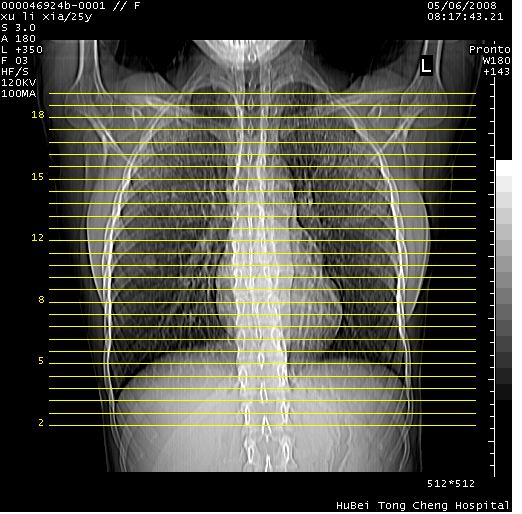

患者 女,25岁。因“左侧卵巢肿瘤”术前胸片偶然发现两肺病变。平素无明显不适,无呼吸系统症状及体征,无传染病史。

cr x线胸片提示:两肺感染性病变(结核可能性大)。

胸部ct轴位平扫(层厚10mm,螺距1.5,重建间隔10mm),图像如下: